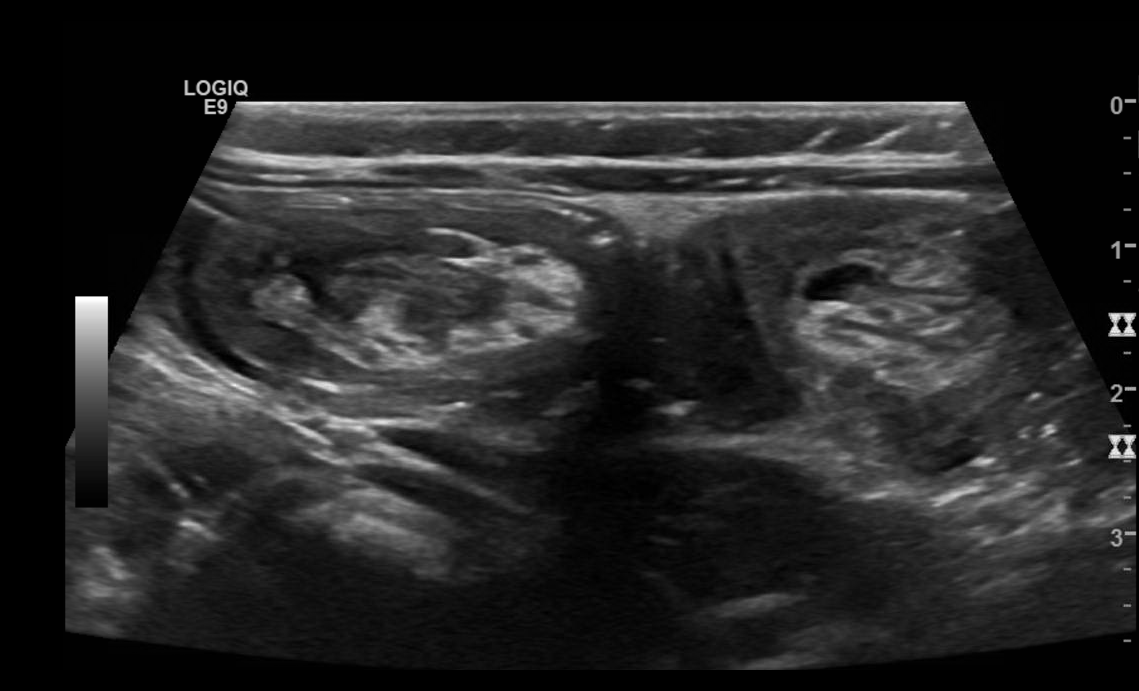

Intussusception